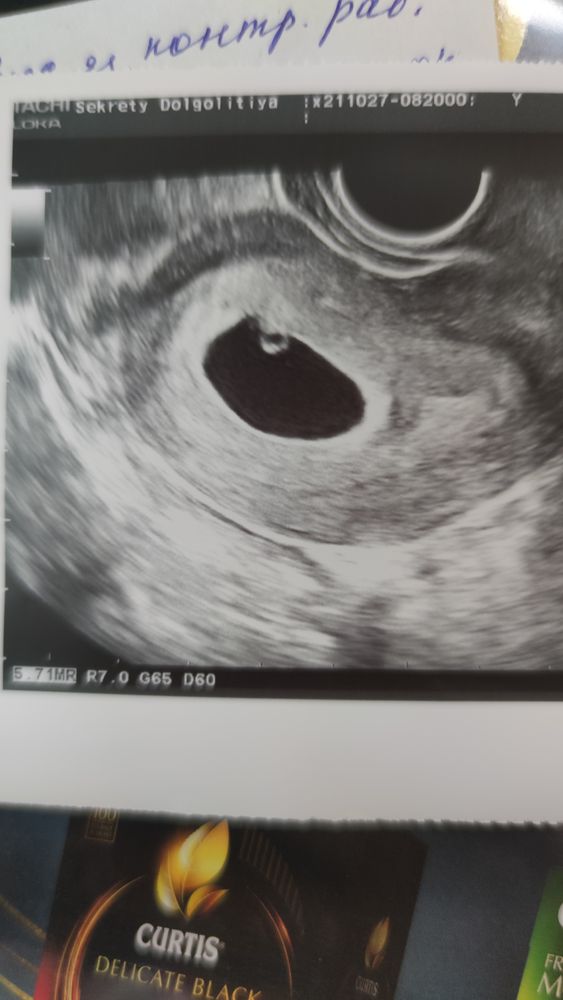

Как вспомню эти чувства... особенно когда ехала на узи думая что все плохо а мне сказали сердечко бьется

Какое чудо! В пять недель и сердечко бьётся. Ростите здоровенькие!!🌷

Лика , нам почти 6. Но я сама очень удивилась. Сегодня рассчитывала только подросшие плодное яйцо увидеть, а тут такой сюрприз